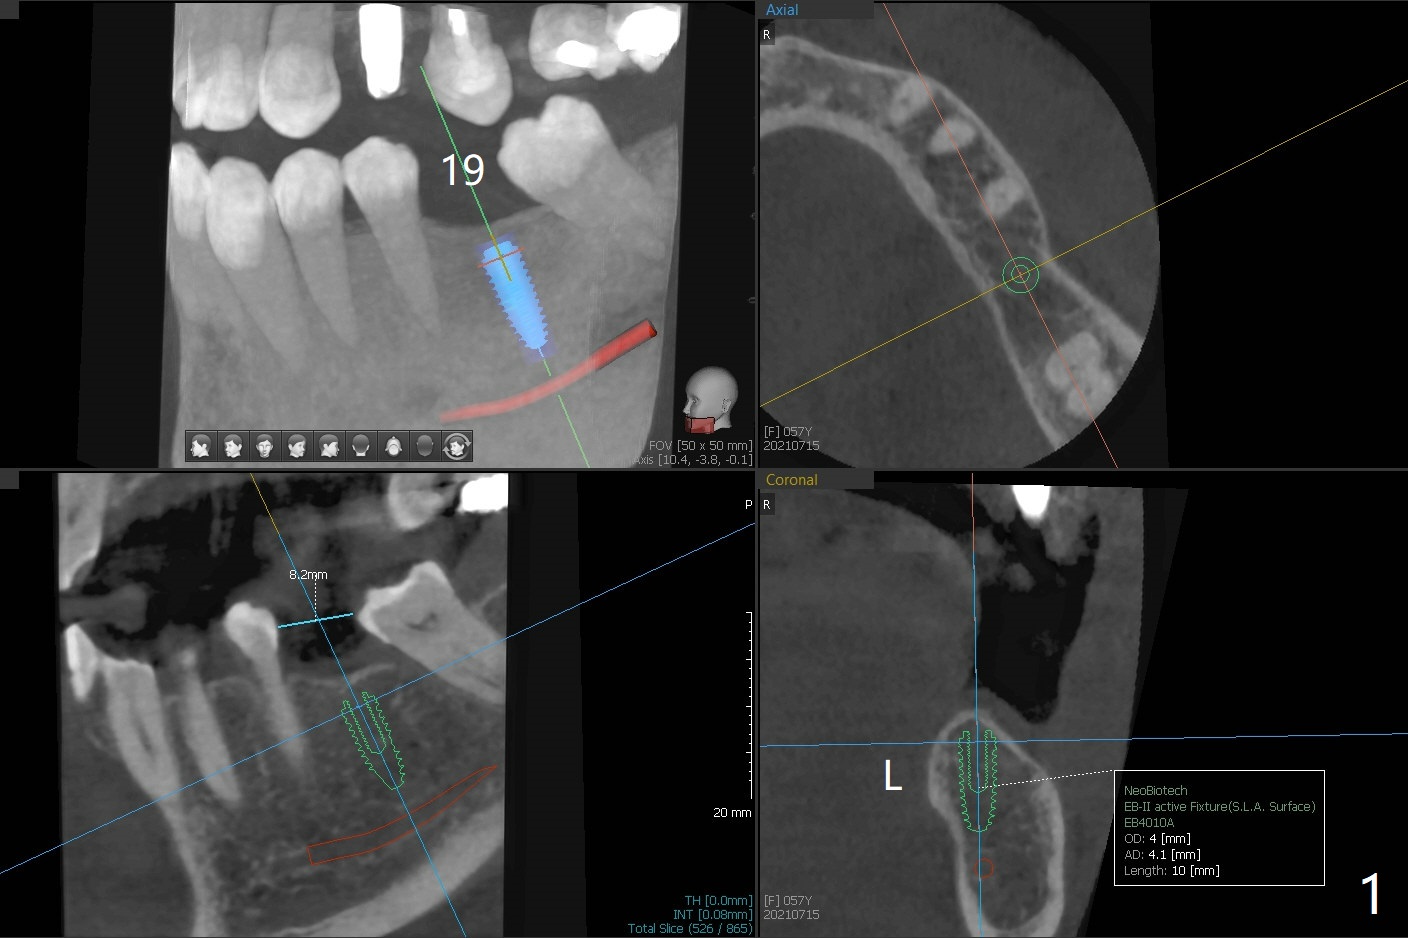

A 57-year-old woman agrees to have #19 implant placed after #12 one and before upper right ones (Fig.1).